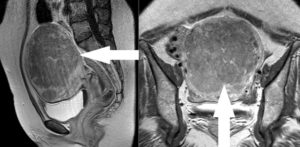

Мрт при болях внизу живота

МРТ органов малого таза

Поскольку болезненность в этой области может быть вызвана множеством заболеваний, обследуют мочеполовую систему и кишечник. У женщины определяют:

- изменение размера, формы и расположения внутренних органов – увеличение, атрофию, отек, смещение, опущение, перекрут;

- наличие воспалительных или опухолевых образований размером от 1,5 мм – их локализацию, форму, размер, степень спаянности с окружающими тканями. Сочетание новообразования с увеличением регионарных лимфоузлов указывает на онкопатологию;

- скопление в малом тазу жидкости, характерно для водянки (асцита), возникающей при заболеваниях почек, печени, злокачественных опухолях. С помощью МРТ определяют наличие крови в брюшной полости;

- пороки развития матки (удвоение, несоответствие размеров), опущение и смещение. При внематочной беременности виден плодный мешок, находящийся в маточной трубе, яичнике, шейке или брюшной полости;

- закупорку просвета кишечника опухолью, желчным камнем, клубком гельминтов, заворот кишок;

- состояние мочевыделительной системы: положение почек, их структуру, проходимость мочеточников, состояние стенок и размер мочевого пузыря, наличие камней и опухолей.

Диагностика проводится на высокопольном томографе силой поля 1,5 Тл. Это дает высокую информативность данных. При обследовании рассматривают органы со всех сторон и даже внутри.

При необходимости размер исследуемого участка увеличивают, чтобы рассмотреть досконально. При МРТ человек не подвергается облучению, а рассмотреть можно сразу несколько органов.

Это увеличивает эффективность исследования, упрощает и облегчает диагностику.